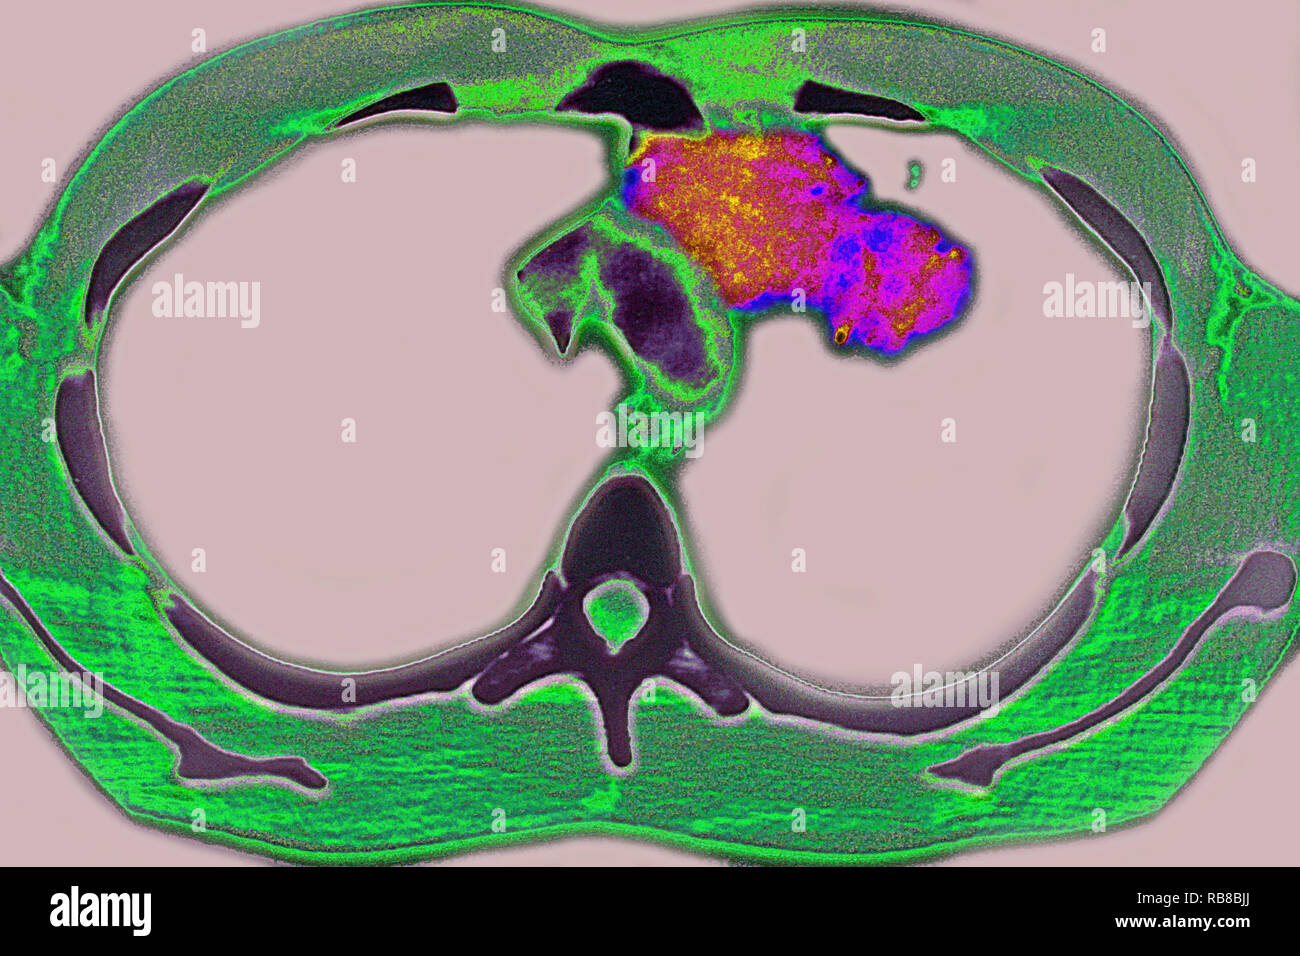

RM2RF8HPX–Pneumonie du poumon droit (infection respiratoire aiguë) révélée par une radiographie thoracique frontale.

RM2RF8HR9–Pneumonie du poumon droit (infection respiratoire aiguë) révélée par une radiographie thoracique frontale.

RM2RF8HPN–Pneumonie du poumon droit (infection respiratoire aiguë) révélée par une radiographie thoracique frontale.